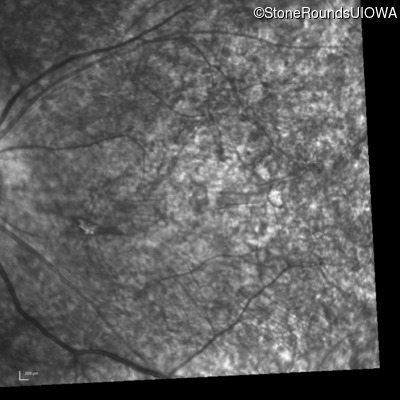

Infrared Fundus Photograph - Right - Count Fingers 3'

Exemplar

Infrared Fundus Photograph - Left - 20/400 sc